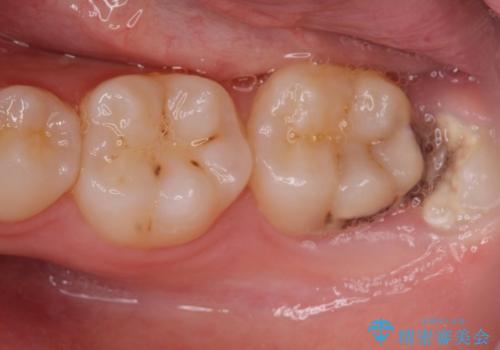

- 歯ぎしりが気になるとの事で来院。

しっかりしたナイトガードが欲しいとの事だったので自費のナイトガードのご案内をしました。

ナイトガードは夜寝ている時、無意識に歯ぎしりをして歯がすり減ることを防ぐことがあります。また、歯が割れたり欠けたりするのも防いでくれます。